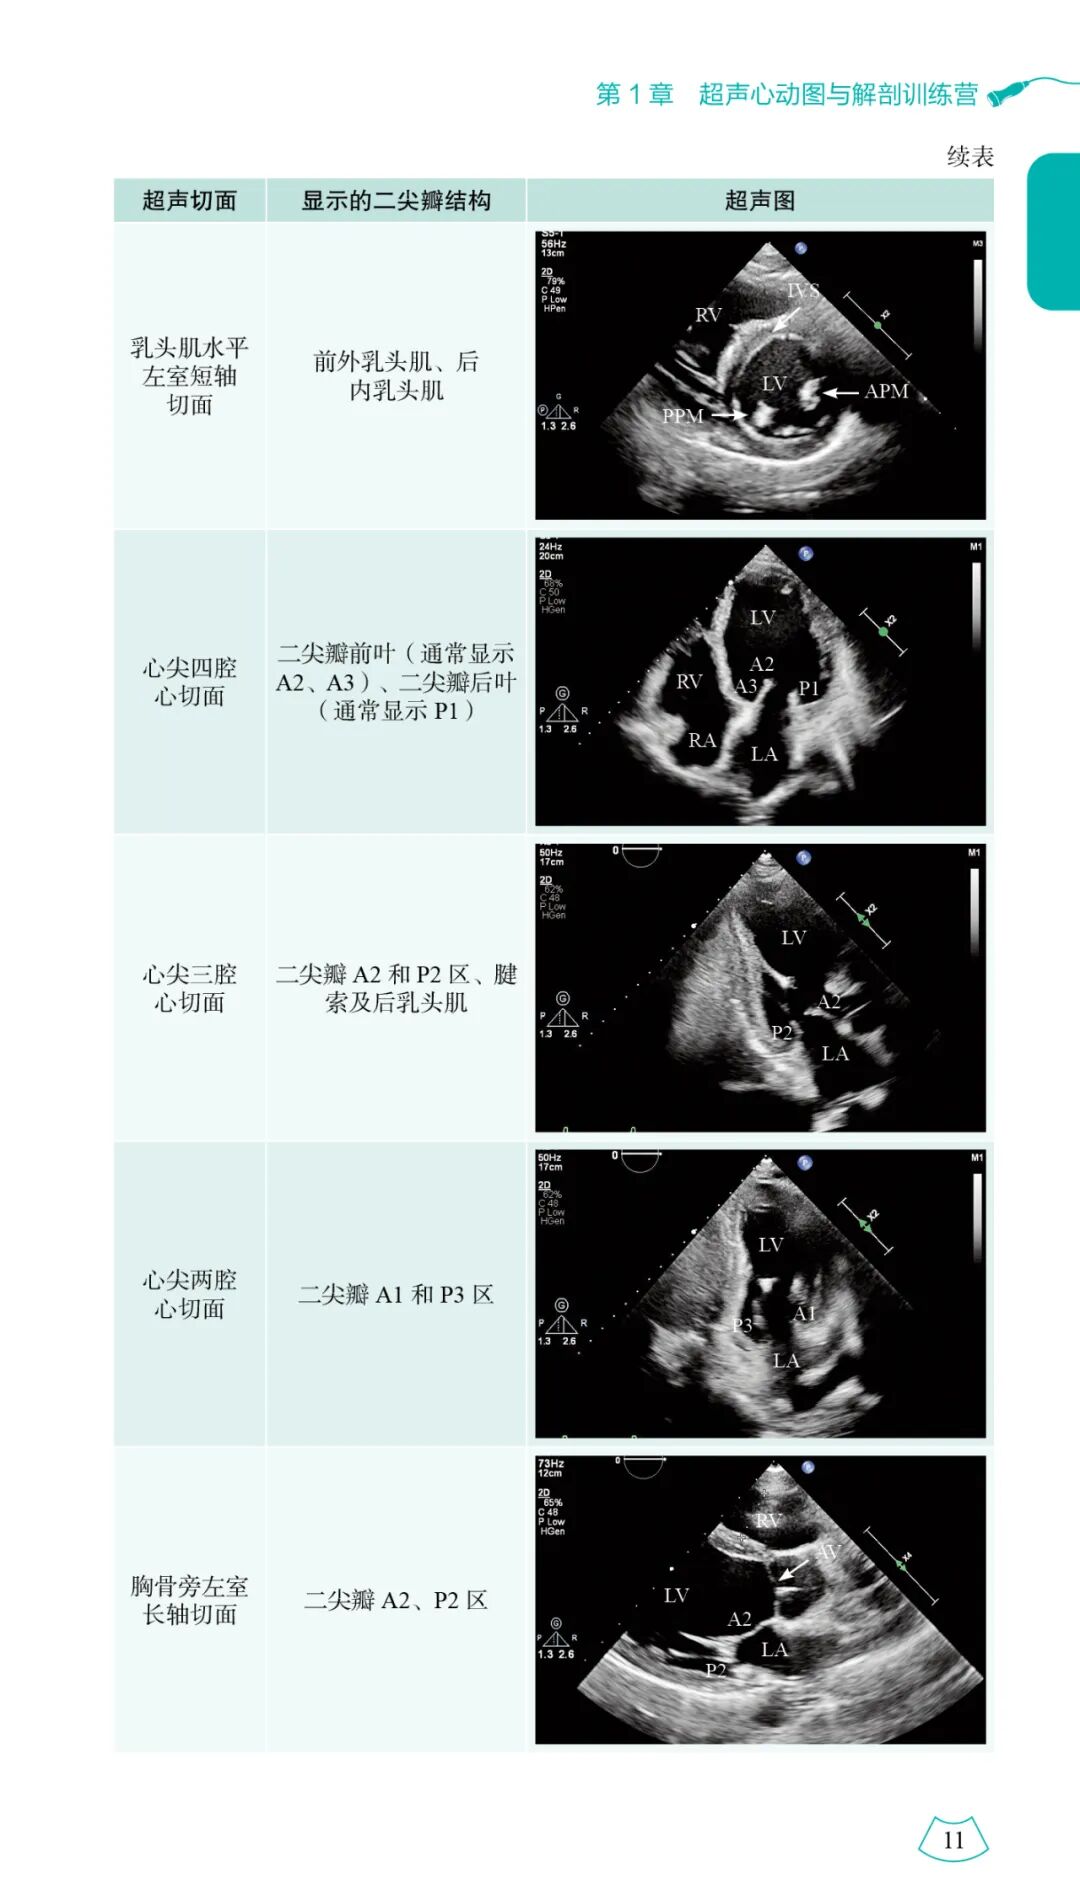

本书详尽阐述了心脏的剖解构造并配以对应的超声图像,从疾病的病理生理出发,剖析心脏的构造和功能改变,将剖解构造、血举止力学转变与临床和超声示意融为一体,以示意图、表格的形式进行总结和升华,轻易读者进一步懂得、把握各类心血管疾病的诊断及分辨诊断。基于超声医师兼顾临床及科研工作的情形,本书采用 “练习营”的形式,经由教授视频、超声人体模型及超声演示等对心血管的剖解构造和各类超声手艺进行介绍,并设定具体的临床配景进行实战练习,以通俗形象的说话讲解心脏疾病的超声诊断思路。

本书参考超声心动图最新指南和共识,涵盖正常心脏的超声剖解、超声心动图常用手艺及超声心动图从常见病到罕有病的诊断方式三大部门。

本书特色光鲜,可总结为“理论的实战和细节的应用”,囊括了好多实用超声新手艺的应用方式,旨在让恢弘超声医师真正把握这门手艺。为实现这个目的,本书全方位具体地介绍了心脏剖解与超声、常见心血管疾病的血举止力学、各类心脏超声手艺的使用方式、常见及罕有心血管疾病的诊断要点等。书中精心绘制了大量剖解构造示意图,拔取了人体模拟器图谱,并用动态视频的形式对心脏超声测量和正常值进行了实战演示,读者经由扫描..即可进行进修,还对各类疾病超声特点及其与临床之间的互相应用进行了总结,让进修加倍直观生动。同时,本团队还深入探究了超声心动图应用的相关细节,测验解决平常工作中“入门易深入难,对理论一知半解”的问题。